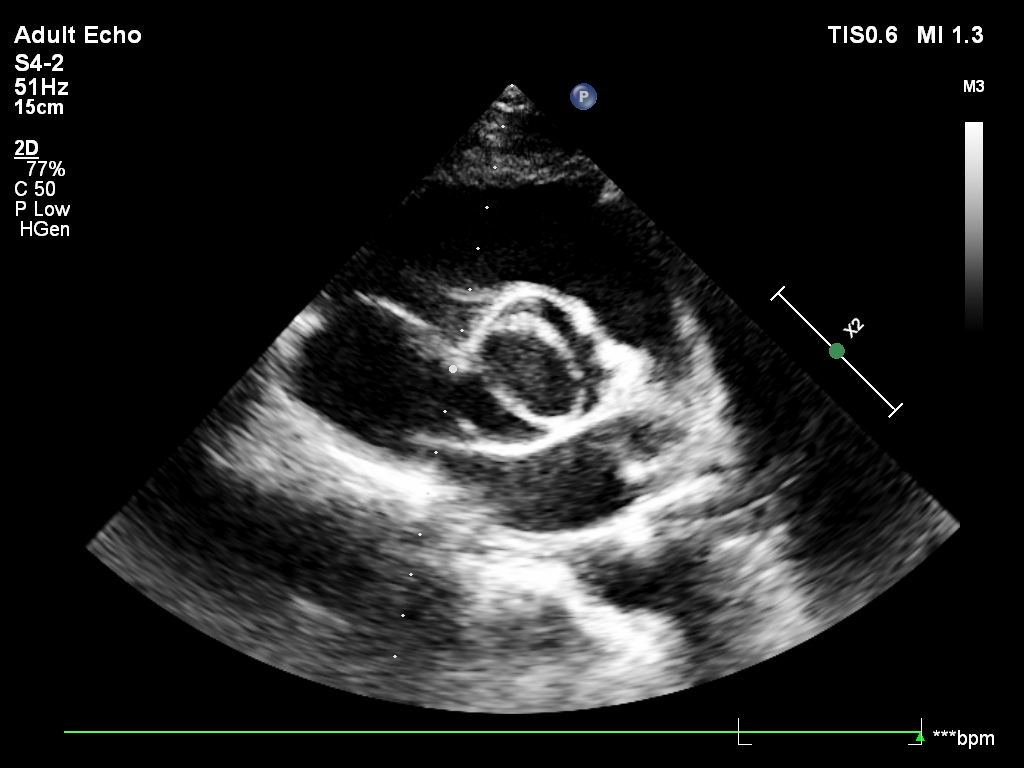

Przypadek 2.A

Przypadek 2.B

Przypadek 2.C